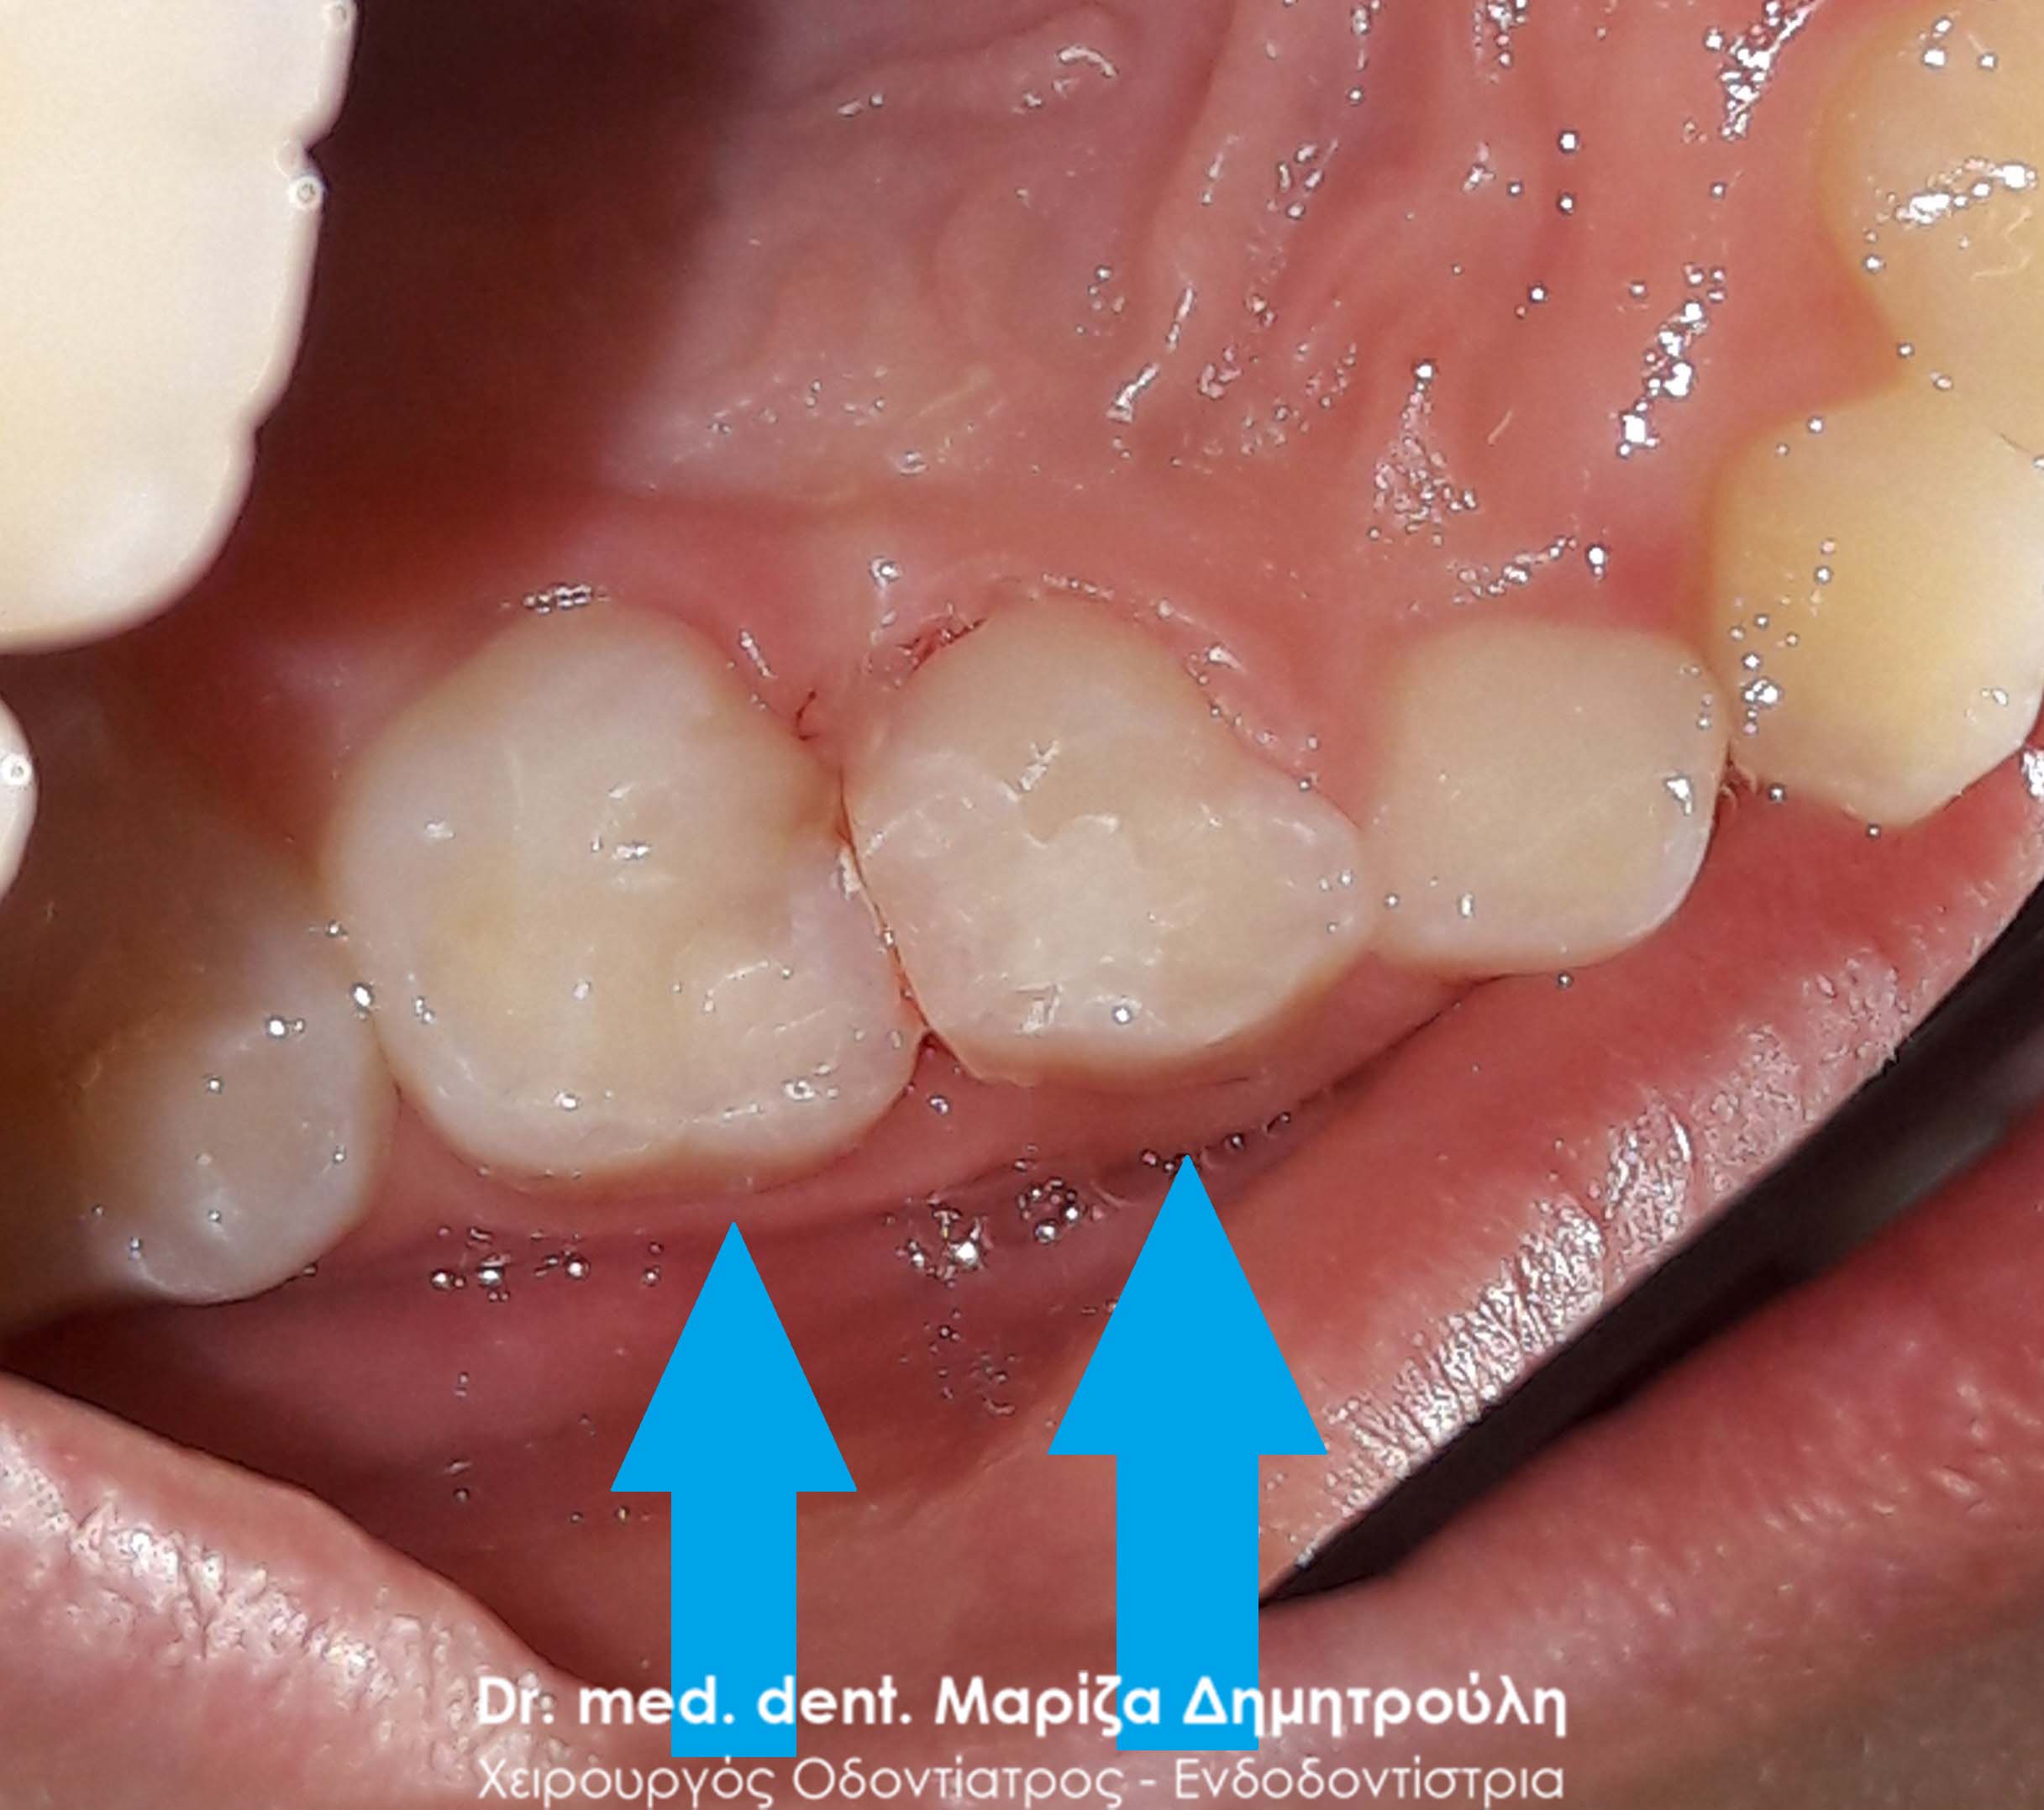

Σε κορίτσι ηλικίας 6 ετών διαπιστώθηκε από τον οδοντίατρο, που επισκέφτηκε το σχολείο, η ύπαρξη 2 τερηδονισμένων δοντιών. Μετά την απομάκρυνση των τερηδονισμένων ιστών από τα 2 παιδικά πίσω δόντια πραγματοποιήθηκαν λευκά σφραγίσματα σύνθετης ρητίνης.

ΠΡΙΝ

ΜΕΤΑ